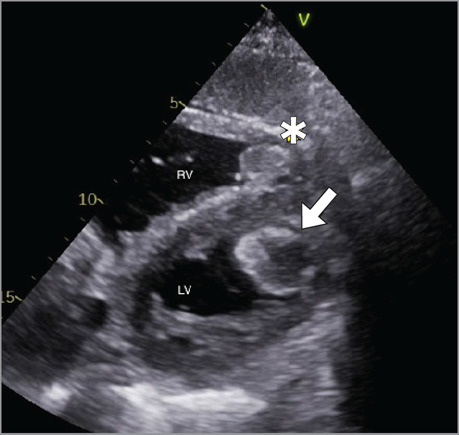

左、右心室同时形成血栓极为罕见,其临床特点及预后尚不清楚。因此,治疗方法仍存在争议。本病例强调了内窥镜取栓术作为治疗心功能受限患者巨大漂浮双室血栓的可行选择的潜力。经主动脉瓣和三尖瓣入路可以有效、完全地清除血栓,从而防止进一步的栓塞并发症。

The simultaneous formation of thrombi in the left and right ventricles is extremely rare, and this condition's clinical characteristics and prognosis remain unknown. Therefore, treatment methods are still controversial. This case highlights the potential for endoscopic thrombectomy as a viable option for the treatment of giant floating biventricular thrombi in a patient with restricted cardiac function. This approach via the aortic and tricuspid heart valves allowed for effective and complete removal of the thrombi, thereby preventing further embolic complications.